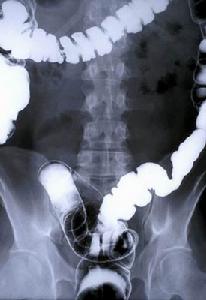

4、X線鋇劑灌腸檢查無陽性發現,或結腸有激惹徵象

4、大腸X線檢查:未見異常,必要時行大腸內窺鏡檢查